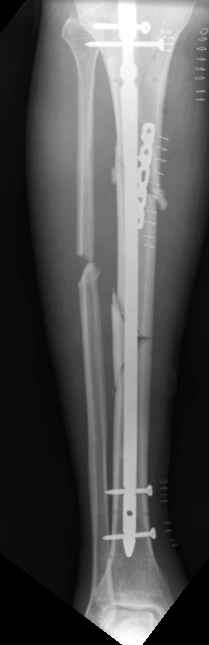

Отправитель: William T Obremskey 20 Декабрь 2003, 12:58

1

2

These can be challenging. I agree w/ all Dr. Carr's points. My preference to prevent the deformity is to use an anteromedial plate. See attached case.

Bill